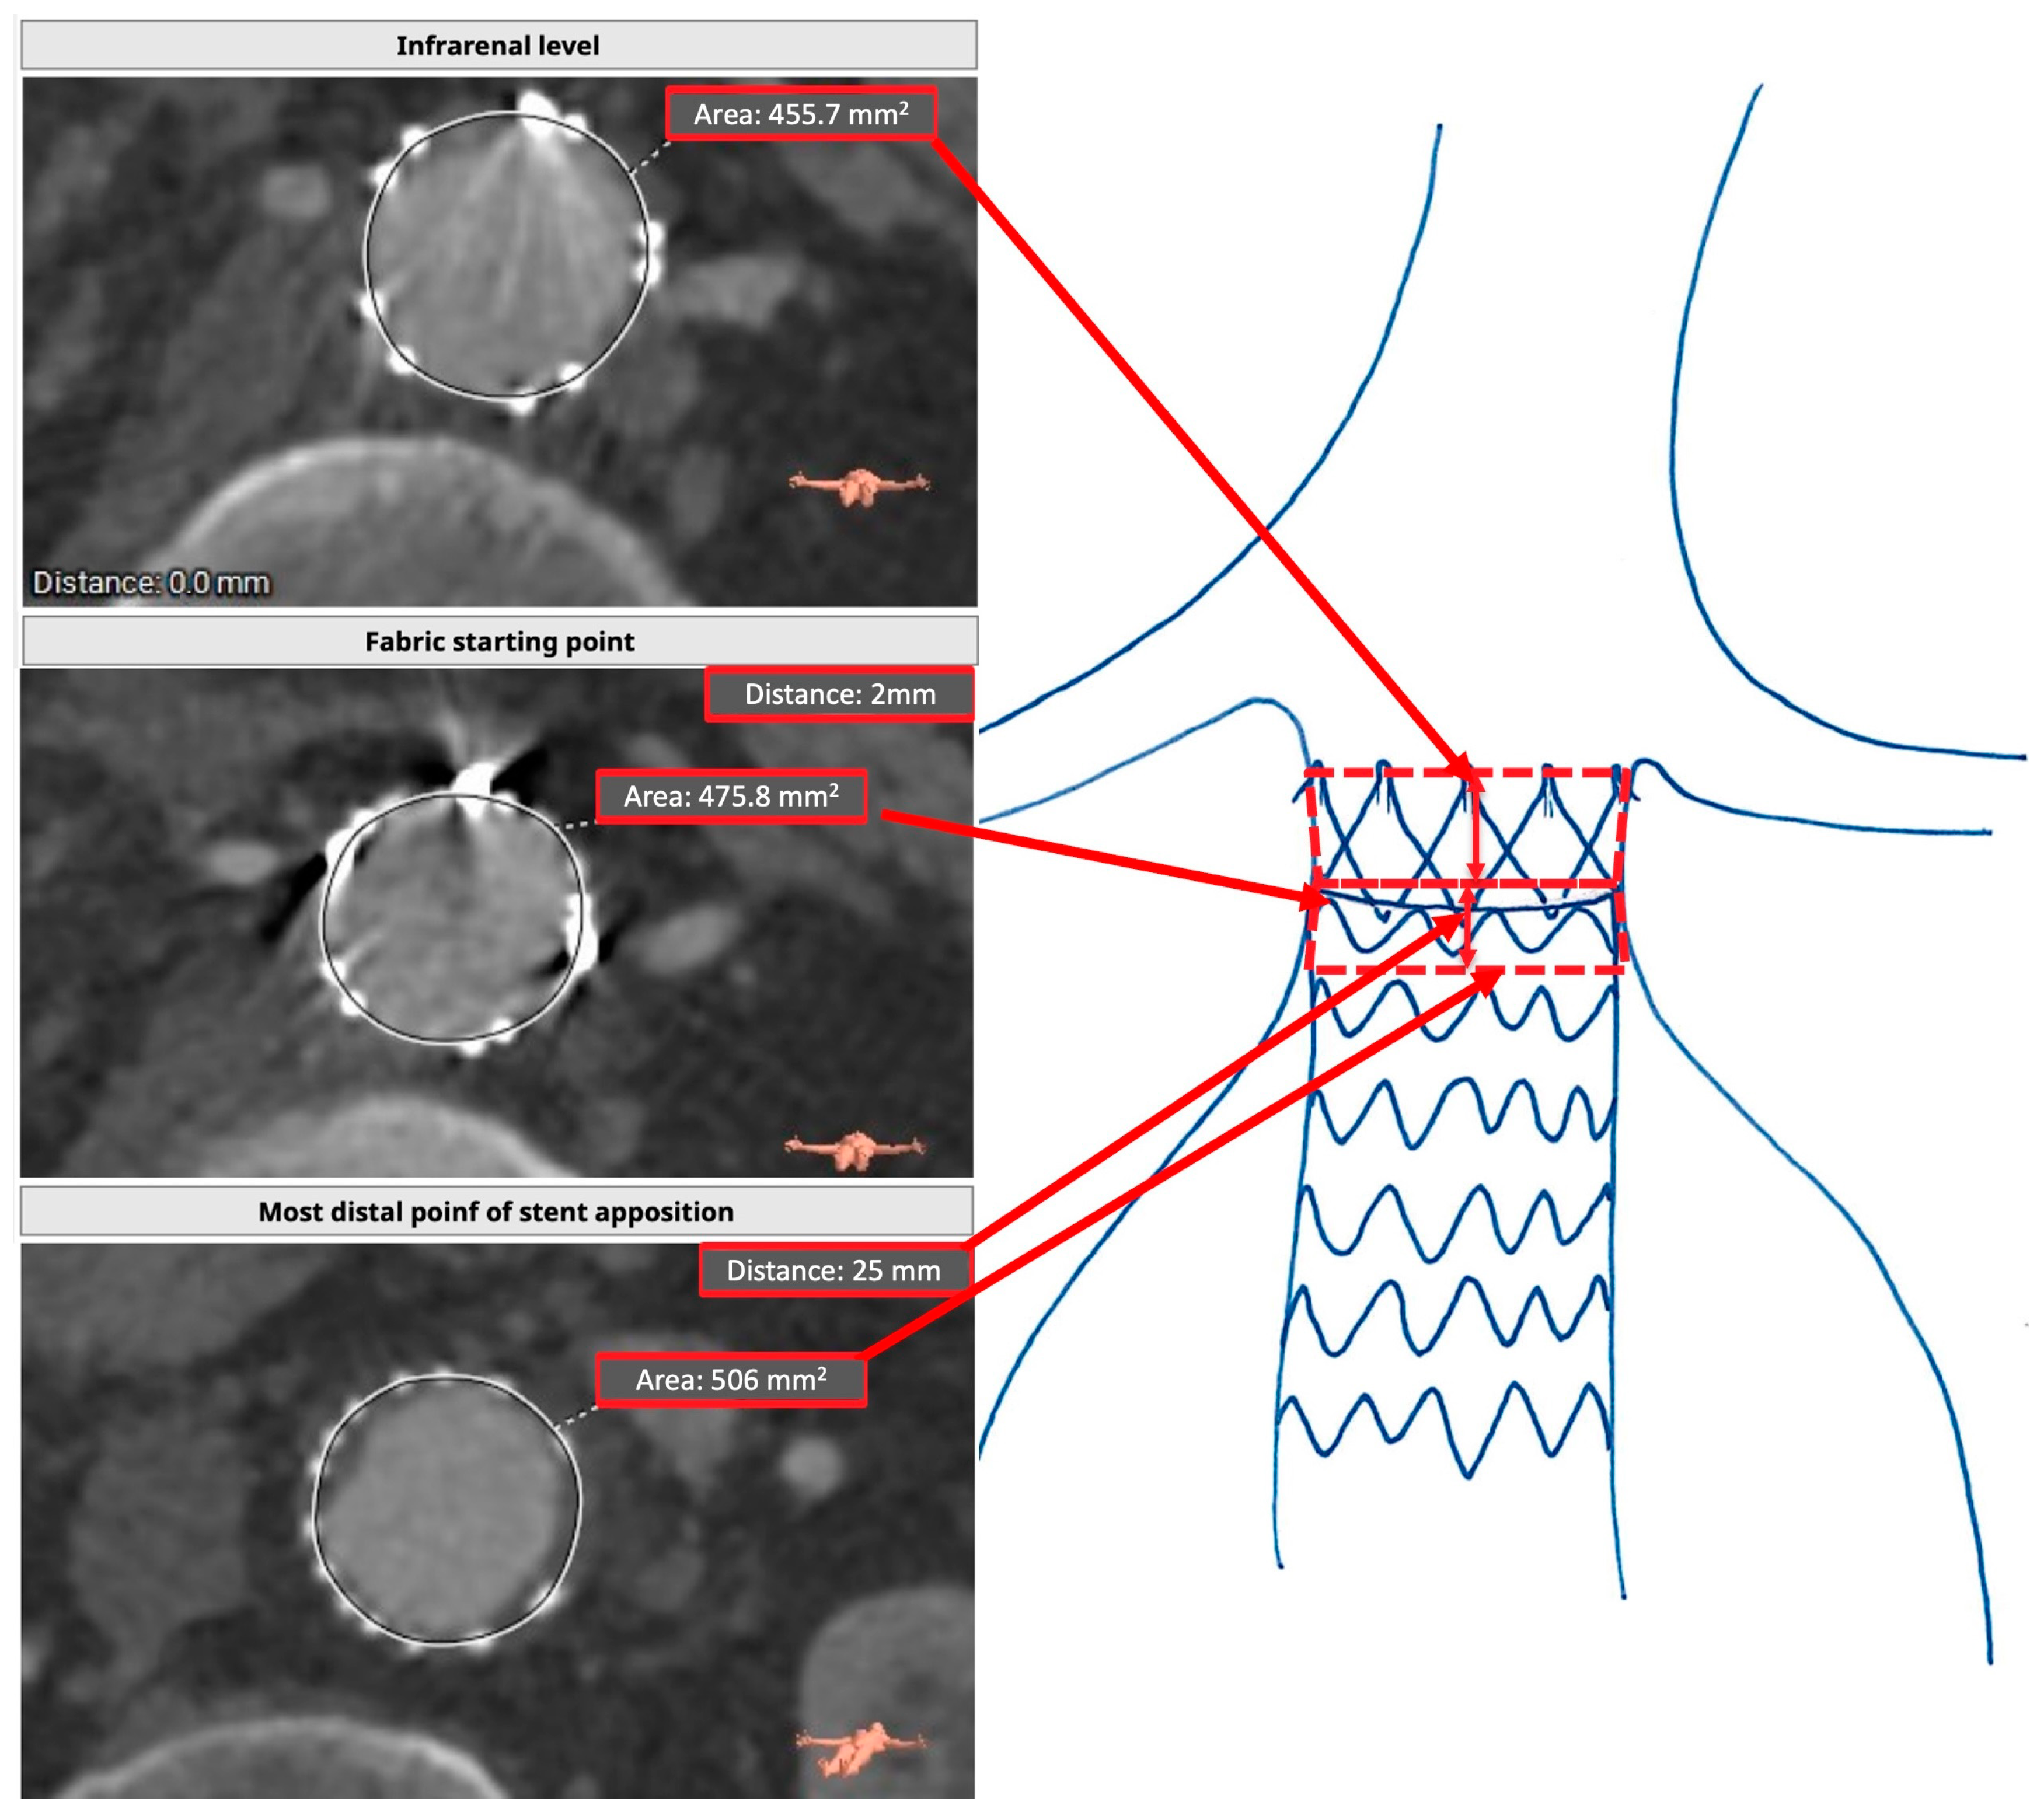

| Preoperative Assessment | Postoperative Assessment | p-Value (<0.05) | |

|---|---|---|---|

| Sealing area (mm2) | 106 (50.0–210.1) | 78 (34–155) | <0.001 * |

| Infrarenal area (mm2) | 37.8 (31.5–47.4) | 38.1 (31.5–45.9) | 0.530 |

| Proximal sealing zone length corrected for graft misplacement (mm) | 15 (7–30) | 11 (4–22) | 0.001 * |

| Most distal point of neck/stent apposition area (mm2) | 43.1 (36.1–52.8) | 40.6 (33.4–51.9) | 0.374 |

| Distance between infrarenal level and most distal point of circumferential stent apposition (mm) | 13.5 (5.2–24) | 15 (7–33) 15 (7–30) if type 1a splits groups | 10 (7.7–13) 8 (8–11) if type 1a splits groups | 0.006 * 0.029 * if type 1a splits groups |

| Distance circumferentially covered by endograft (mm) | 11 (4–22) | 12 (4–22) 12 (4–22) if type 1a splits groups | 6 (3–20) 2.5 (0.5–10) if type 1a splits groups | 0.155 0.027 * if type 1a splits groups |

| Most distal point of circumferential stent apposition area (mm2) | 40.6 (33.4–52.0) | 39.9 (33.0–51.3) 40.9 (33.5–52.1) if type 1a splits groups | 46.2 (34.6–62.4) 36.6 (25.7–47.8) if type 1a splits groups | 0.855 0.191 if type 1a splits groups |